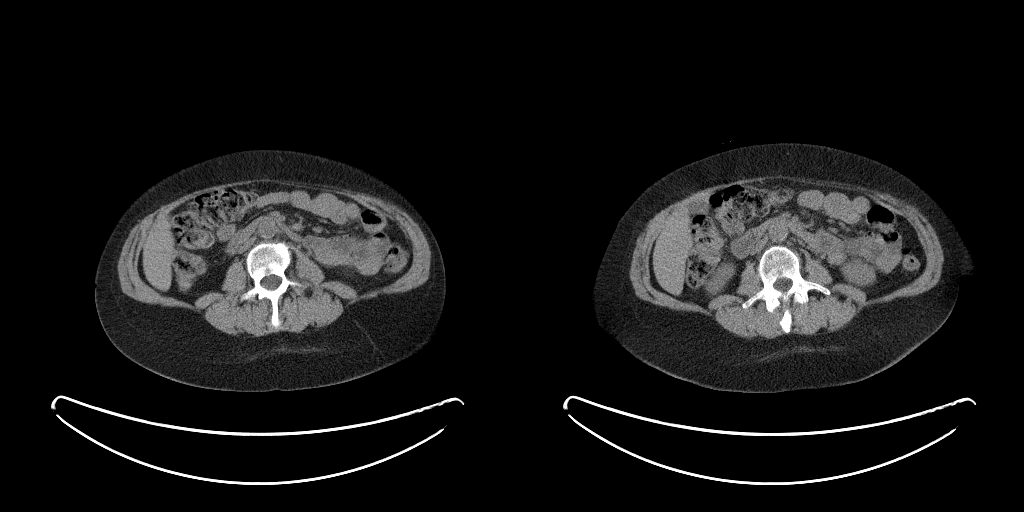

The full validation was then performed on Dataset B treating the two models as a single process that takes in a full abdominal CT series and produces estimates of body composition in terms of square cross-sectional area of muscle, subcutaneous fat, and visceral fat. In this case, the DSC is not an appropriate measure because the segmentation may be performed on a different slice from the ground truth mask. Table 2 compares the accuracy of the different tissue types and Figure 3 shows some example outputs.

The mean absolute localization error on the Dataset B test set was , which lies within the range of the L3 vertebra on the majority of patients.